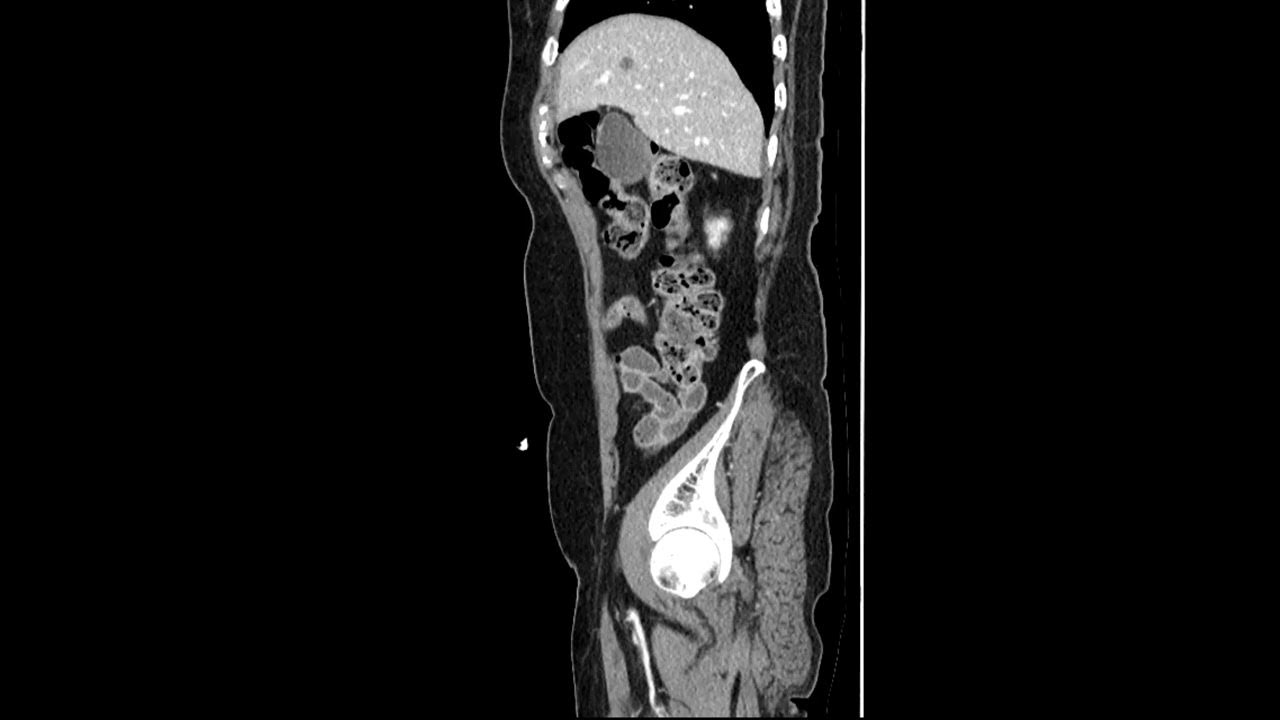

From www.youtube.com

Renal Stone Ultrasound, Radiolucent Renal Stones YouTube Radiolucent Stones Ct Web urinary matrix stones are a rare form of urinary calculi that are typically radiolucent. Web if an unenhanced ct is insufficient to delineate the difference between a phlebolith or a urinary calculus, a delayed. Web conventional radiography may be helpful in visualizing larger stones, once they are identified on ct scans, to provide a baseline to follow. Web the. Radiolucent Stones Ct.